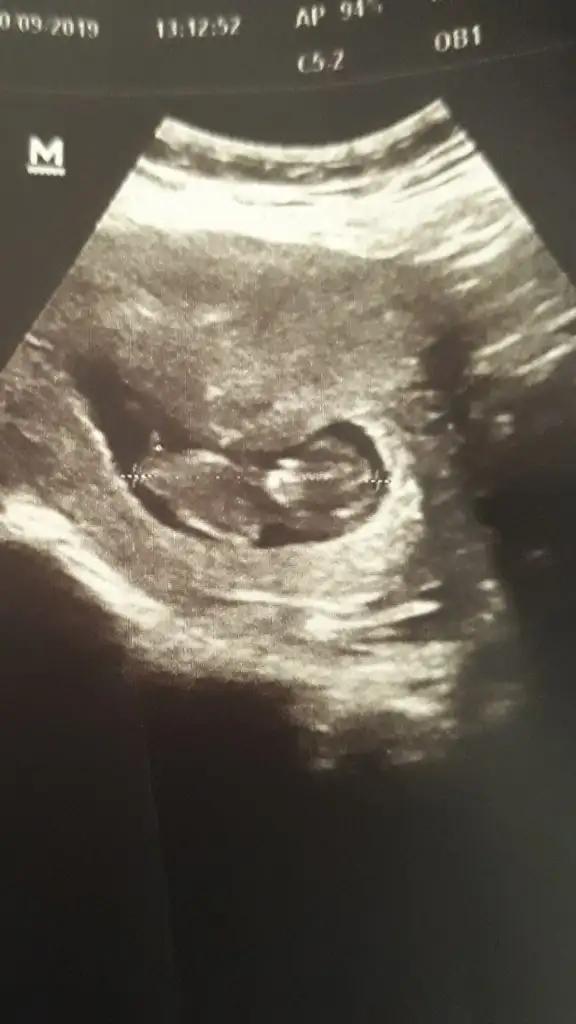

Daha netini çekebilirsem paylasacagim tekrar :) Doktorda bacak arasinda bir sey goremedim ama bidahakine belli olur dedi. Ultrasonda 12 haftalik cikiyor ama regl tarihime gore 10+5Kıza gibi net usg yokmu çok net degil kaç haftalık 11 yada 12 olmalı

Kizz11 hafta iki günlük sizce nedir

KizzzNe diyorsunuz hanımlar